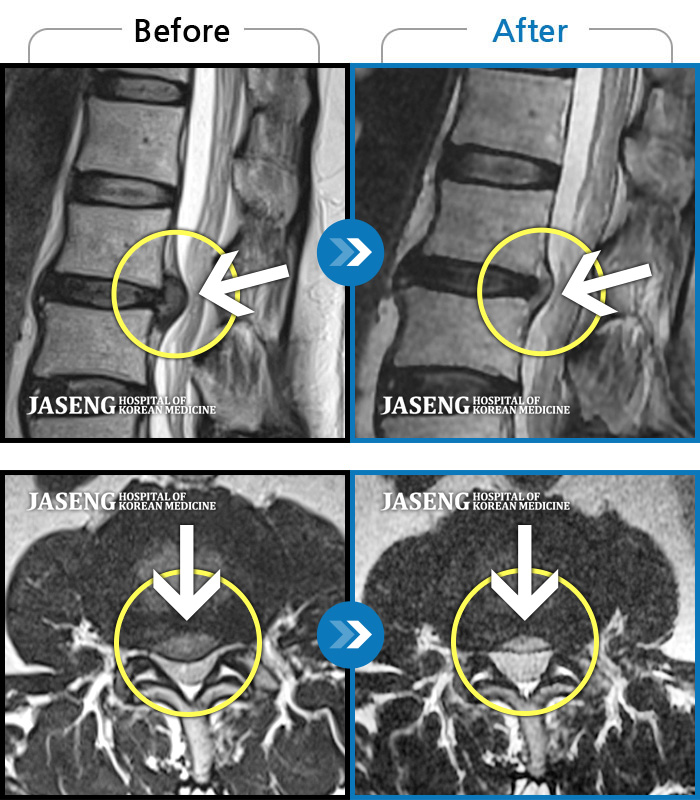

MRI로 보는 치료결과

1,169건의 MRI 전후 사진으로

터진 디스크 흡수 사례를 확인하세요.

[촬영시기:22.05.27~24.11.02]

[촬영시기:22.05.27~24.11.02]

[천안_허리디스크] 직업 상 무거운 물건을 많이 드는 편으로 6개월간 허리와 둔부의 통증이 지..조회수 3 2024.11.21